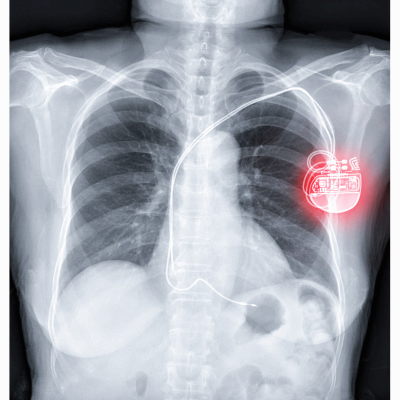

알려져 있는 치료 과정에는 약물 치료와 심박수 조율기가 있습니다. 자세한 치료과정이나 방법은 알 수 없지만